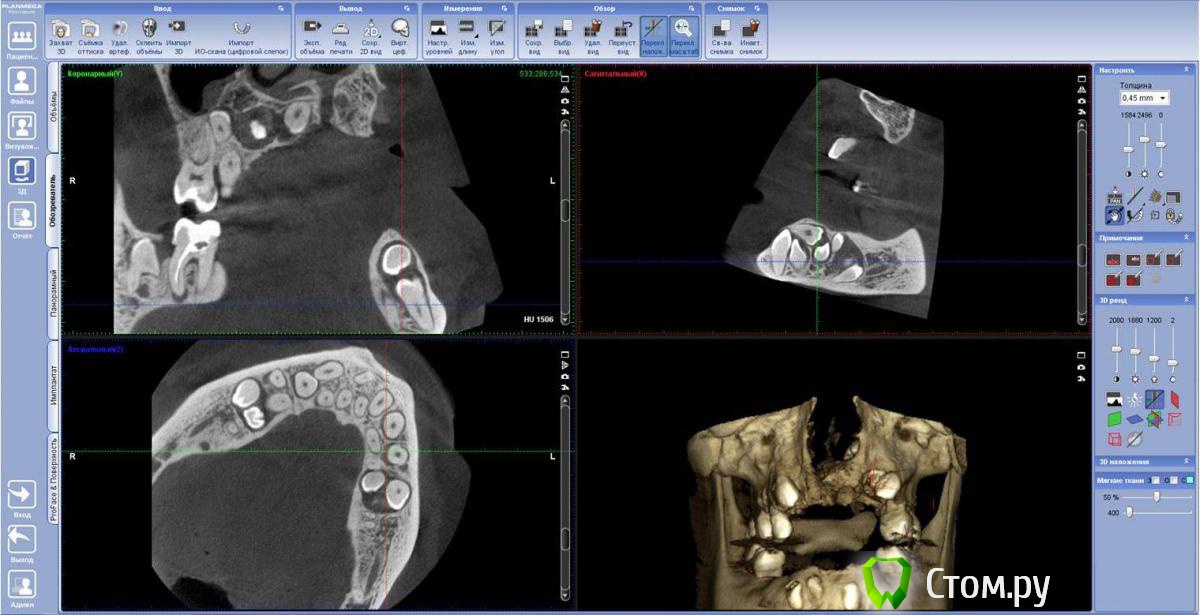

FBR Опубликовано 28 января, 2014 Поделиться Опубликовано 28 января, 2014 (изменено) Планируется протезирование на имплантатах ( в перспективе). Оперировать 1 этап (удаление зубов), планируем с ЛОРом. Изменено 28 января, 2014 пользователем FBR Ссылка на комментарий

FBR Опубликовано 29 января, 2014 Автор Поделиться Опубликовано 29 января, 2014 Красота. А сколько лет пациенту?34 года. Пока по плану с лором определяемся. Думаю убрать слева зубы с минимальной травмой кости. 25 лежит в носу и частично в кисте. Ссылка на комментарий

FBR Опубликовано 29 января, 2014 Автор Поделиться Опубликовано 29 января, 2014 to FBRрасщелина скрытая, или есть "сквозняк" ?Там и расщелины нет Ссылка на комментарий

kriokov Опубликовано 29 января, 2014 Поделиться Опубликовано 29 января, 2014 Там и расщелины нетпо аксиальному значит я не правильно понял, подумал за скрытую расщелину Ссылка на комментарий